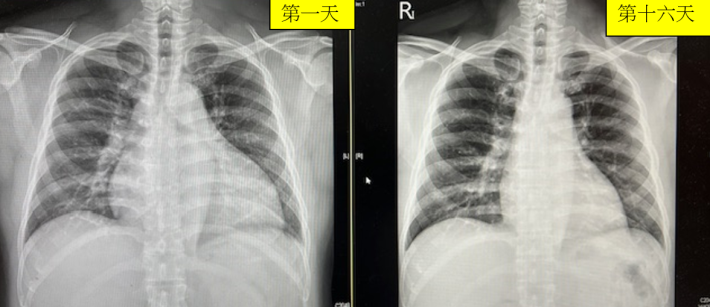

發稿日期:114年2月20日 心臟衰竭是一種嚴重且常見的心血管疾病,指心臟無法有效地供給血液來滿足全身的代謝需求。心臟擴大(Cardiomegaly)是心臟衰竭的一個常見表現,指心臟的結構性改變,例如心室或心房的異常擴張。過往一旦心臟擴大要再回復原本正常大小並不常見,但隨著藥物演進及各式心衰竭治療的進步,心臟瘦身成功的例子變得越來越多了起來。 臺北市立聯合醫院陽明院區心臟內科主任曾梓維表示,最近半年之中就有兩位年約40至50歲的男子,長期三高不控制因此心臟衰竭造成呼吸困難、無法平躺睡以及全身水腫的病人來到門診及住院治療,經藥物治療後,不只心衰竭症狀改善,心臟擴大在16天之內回復正常大小,心臟收縮力(LVEF,left ventricular ejection fraction)也由使用藥物前的28%上升到48%的案例。可見近代心衰藥物及治療確實有了長足進步。 曾梓維說,心臟擴大的成因多種多樣,常見包括:高血壓、冠狀動脈疾病、心肌病變(如擴張型心肌病)以及瓣膜疾病等。這些情況導致心臟需要承擔額外負擔,最終導致心臟結構改變並影響其功能。 心臟衰竭通常分為兩類:收縮功能不全(HFrEF),心室無法有效收縮;以及正常收縮分率型(HFpEF),心室無法有效舒張填充血液。這些改變進一步加劇心臟擴大的進程。 患者常出現症狀包括: • 呼吸困難,尤其是在活動或平躺時。 • 下肢水腫或體重短期內增加。 • 持續性的疲倦與運動耐受力下降。 診斷方面,醫生通常會利用胸部X光檢測心臟大小,心電圖評估是否有冠狀動脈狹窄或阻塞,心臟超音波則能詳細觀察心室心房及瓣膜的結構和功能。核磁共振(MRI)有助於進一步分析心臟肌肉的健康狀態。此外,血液檢查中BNP(B型利鈉蛋白鏈)的升高也是心臟衰竭的一項參考指標。 心臟擴大和心臟衰竭的治療以改善症狀、延緩疾病進展為目標。常見治療方法包括: • 藥物治療:目前四大支柱的用藥 1. 血管張力素轉化酵素抑制劑(angiotensin converting enzyme inhibitor,ACEI)及血管張力素接受器拮抗劑(angiotensin Ⅱ receptor blocker,ARB)能減輕心臟的負擔。 2. β阻斷劑有助於穩定心率。 3. 第二型鈉-葡萄糖轉運通道抑制劑(sodium-glucose co-transporter 2 inhibitor,簡稱SGLT2抑制劑)排糖減鈉同時保護腎臟。 4. 礦物皮質酮受體拮抗劑MRA(Mineralocorticoid/ Aldosterone receptor antagonists,MRAs)可排鈉排水。 • 手術治療:針對瓣膜疾病的修復或置換手術,針對冠狀動脈疾病可安排心導管手術放置支架或透過心臟再同步治療(cardiac resynchronization therapy,CRT)改善心臟的收縮泵血功能。 曾梓維指出,預防心臟擴大和心臟衰竭的關鍵在於控制危險因子,如:高血壓、高血脂和糖尿病。此外,定期健康檢查和早期發現異常心臟功能,有助於減少疾病的發生風險。生活方式改變及調整也很重要包含減鹽飲食、控制體重和戒菸限酒有助於減輕心臟壓力。 心臟擴大和心臟衰竭雖然嚴重,但通過現代醫療技術與生活方式的改變,患者的生活品質可望顯著改善。及早注意症狀並尋求專業醫療協助,對於疾病的管理至關重要。